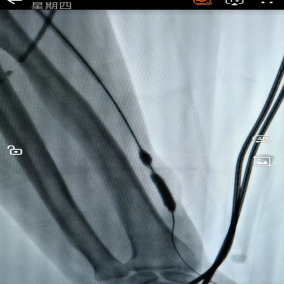

12月10日,贵州航天医院第87次晨读会由我院肾脏风湿科副主任医师谢谋进作学术交流,她以“系统性红斑狼疮”为题,全面讲解了该疾病的定义特征、临床表现与诊断标准、治疗原则及最新指南推荐等内容,并介绍了针对不同疾病活动指数的分层管理、非药物干预要点以及特殊阶段注意事项,为临床深化对该疾病的综合理解与规范实践提供了有益借鉴。 肾脏风湿科专家简介 冯远军 肾脏风湿、肝胆外科党支部书记,肾脏风湿科主任,主任医师 临床擅长:对慢性肾脏病、急性肾损伤、急慢性肾小球肾炎、肾病综合症、风湿性疾病、间质性肾炎、肾小管损伤等疾病的诊治及血液透析技术、动静脉内瘘成形术及疑难病例的诊治具有丰富的临床经验。 曾在上海市第一人民医院及贵阳市第一人民医院进修学习,贵州省医学会肾脏病学分会第五届委员会委员,遵义市医学会肾脏病学分会第一届委员会副主任委员,遵义市医学会风湿病学分会第一届委员会副主任委员,荣获“贵州航天劳动模范、遵义市汇川区先进工作者”,遵义市医疗事故鉴定专家库成员,主持省市级科研项目4项,完成4项,近5年发表论文10余篇,北大核心期刊1篇。 王卫华 肾脏风湿科主任医师 临床擅长:从事临床工作28年,擅长尿毒症患者血管通路的建设及维护(如标准和高位动静脉内瘘术、取栓+内瘘重建术、内瘘狭窄球囊扩张术、长期中心静脉置管术及肾穿刺活检术)等手术,对原发性和继发性肾病综合征、急、慢性肾小球肾炎、慢性肾脏病、泌尿系感染、结缔组织病、急性中毒、痛风、贫血、血小板减少症等疾病诊治及血液透析技术应用等具有丰富的临床经验。 1995年毕业于遵义医学院临床医学系,曾前往重庆医科大学进修学习肾脏疾病及血液净化,遵义市医学会肾脏病学分会常务委员,遵义市血液净化质量控制中心委员,先后发表肾病专业省部级医学刊物医学论文8篇,主持市级科研项目2项。 李丽华 中共党员,肾脏风湿科副主任医师 临床擅长:从事临床工作17年,对慢性肾脏病、急性肾损伤、急慢性肾小球肾炎、肾病综合征、风湿性疾病、间质性肾炎、肾小管损伤、急慢性肾衰竭的血液透析、CRRT治疗以及血管通路的建设维护等具有丰富的临床诊疗经验。 2006年毕业于遵义医学院临床专业,曾在遵义医学院附属医院完成住院医生规范化培养,并前往第三军医大学新桥医院、珠海市人民医院进修学习,中华医学会遵义市肾脏病学分会委员,遵义中医药学会肾病专业委员会委员,遵义市血液净化质量控制中心委员,遵义市医学会血液学分会委员会委员,发表省部级医学刊物医学论文4篇,主持参与省级科研课题1项,主持参与市级科研课题1项,院级新技术6项,获得本专业授权实用新型专利3项。 李 玫 中共党员,肾脏风湿科副主任医师 临床擅长:从事临床工作15年,对慢性肾脏病、急性肾损伤、急慢性肾小球肾炎、肾病综合征、风湿性疾病、间质性肾炎、肾小管损伤等疾病的诊治具有丰富的临床经验,擅长血液透析技术、动静脉内瘘成形术等。 2008年毕业于遵义医学院临床医学系,曾前往遵义医学院附属医院进修学习肾脏病与血液净化相关技术,遵义市医学会肾脏病学分会委员,发表肾病专业省部级医学刊物医学论文4篇。 谢谋进 中共党员,肾脏风湿科副主任医师 临床擅长:对肾脏风湿科常见病、多发病的诊治具有丰富的临床经验,特别擅长急、慢性肾小球、肾病综合征、系统性红斑狼疮、类风湿性关节炎、干燥综合征等疾病的诊疗,并熟练掌握CRRT、血液透析及血管通路的建立。 2010年毕业于遵义医学院临床医学系,2013年在遵义医学院附属医院完成住院医师规范化培训,曾前往四川大学华西医院进修学习;中国医师协会肾脏内科医师分会会员,遵义市医学会血液学分会委员会委员;发表省部级医学刊物、医学论文及科技核心论文数篇;主持参与院级新技术4项。 肾脏风湿科简介 基本情况 贵州航天医院肾脏风湿科2017年建立,住院患者承载能力达到50人左右,透析治疗服务惠及280余人的患者群体,在学科建设、高端医疗设备引进及专业技术队伍已达到区域内领先水平。科室共有医护人员46名,副高级以上专家7名,亚专业设置齐全,涵盖肾脏疾病、风湿免疫疾病药物治疗、透析治疗及透析通路维护等多个专业领域,为患者提供全面、精准、高效的诊疗服务。配备了尖端的医疗设备与智能化的辅助系统,包括透析机、CRRT机等设备。 专科特色 (一)肾脏病治疗领域:专精于血液透析、血液透析滤过、血液灌流、血浆置换、CRRT等尖端技术,致力于为患者量身打造个性化的肾脏替代治疗方案。 (二)在风湿病治疗方面:凭借生物制剂、免疫抑制剂等前沿药物,结合患者的具体情况,精心策划个体化的治疗策略,有效减轻患者症状,显著提升生活质量。 超声引导下球囊扩张术:内瘘狭窄是内瘘最常见的并发症之一,我们采用先进的超声引导下球囊扩张术,通过微创方式恢复内瘘通畅,有效避免了传统手术带来的创伤和痛苦。 内瘘血栓溶栓治疗、取栓术:血栓形成是内瘘功能丧失的主要原因之一,根据患者具体情况,采用溶栓治疗、取栓术等多种手段,确保患者及时恢复透析治疗。 内瘘动脉瘤形成治疗:动脉瘤是由于内瘘局部血流动力学改变引起的血管扩张性疾病,采取佩戴弹力绷带、手术修复等措施,防止动脉瘤进一步发展和破裂。 内瘘感染治疗:内瘘感染是内瘘并发症中最为严重的类型之一,一般采用敏感抗生素进行抗感染治疗,严重者采取手术清创等措施。 内瘘窃血综合征治疗:是由于内瘘建立后,远端肢体血流减少引起的一系列症状,通过调整透析方案、改善内瘘血流分布及必要时重建内瘘等措施,有效缓解患者的症状并提高其生活质量。 诊疗范围 擅长治疗急慢性肾炎、肾病综合征、肾衰竭等肾脏疾病;擅长治疗类风湿关节炎、系统性红斑狼疮、干燥综合征等风湿免疫性疾病,并为患者提供健康教育与康复指导,帮助患者更好地管理疾病,提高生活质量。 end